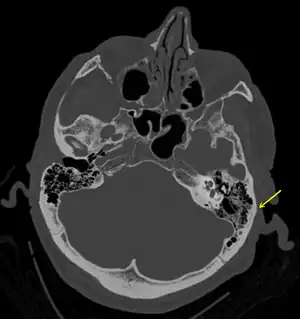

Temporal bone fractures

Acute injury to the internal carotid artery (carotid dissection, occlusion, pseudoaneurysm formation) may be asymptomatic or result in life-threatening bleeding. They are almost exclusively observed when the carotid canal is fractured, although only a minority of carotid canal fractures result in vascular injury. Involvement of the petrous segment of the carotid canal is associated with a relatively high incidence of carotid injury.[11]